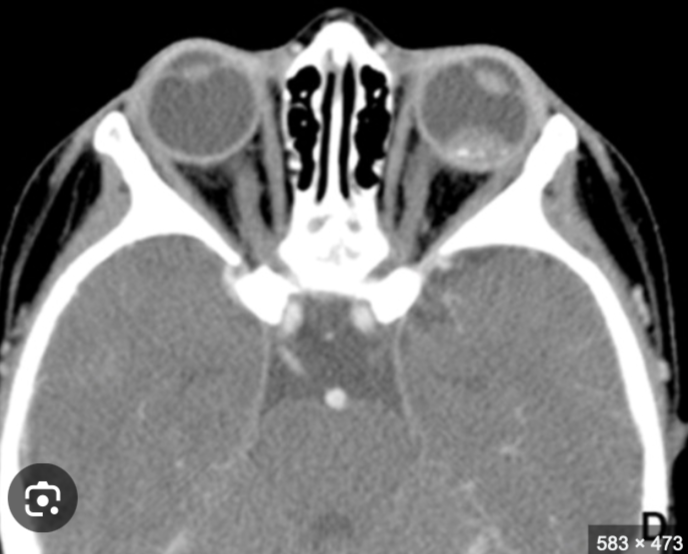

13

Q

Calcificación “manchada” o punteada en globo ocular

Masa con densidad intermedia

Contraste

A

RB en TC

14